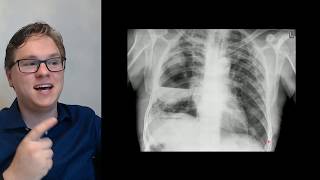

aqui também E logicamente que haverá um aumento do diâmetro anteroposterior do tórax Por uma questão aí geométrica então no tórax enfisematoso você terá a redução das forças elásticas do pulmão elevação das costelas elevação do externo e aumento do diâmetro Antero posterior do tórax uma consequência natural dos os processos mecânicos e geométricos da caixa torácica temos aqui uma radiografia de tórax normal Eh vamos prestar bastante atenção no contorno do diafragma veja que o diafragma faz esse Contorno convexo Contorno convexo do diafragma aqui no perfil veja o diafragma o m diafragma direito fazendo o contorno convexo dele

e o m diafragma esquerdo também fazendo o seu Contorno e o espaço retro external que é área de pulmão que fica atrás do externo entre o externo e o coração veja que ele é relativamente pequeno uma faixa lentiforme eí relativamente pequena agora a radiografia de um paciente com enfisema pulmonar um enfisema já avançado né Lembrando que na radiografia vai aparecer sinais de enfisema Apenas quando este já estiver avançado nas fases iniciais você vai ter uma radiografia fia praticamente normal nós temos um aumento aqui do comprimento do pulmão nós temos uma retificação do diafragma essas ondulações

aqui elas não são não é derrame plural não é apagamento do seio costofrênico são as inserções do diafragma Nos Arcos costais veja que o diafragma deveria estar fazendo isso aqui deveria est fazendo isso aqui Quando ele retifica quando ele abaixa às vezes até inverte ele mostra as inserções as suas inserções músculo tendíneas nas costelas e dá Esse aspecto aqui ondulado pequenas ondas veja aqui no perfil retificação completa do diafragma diafragma retificado às vezes até ele pode até inverter e outro aspecto O importante aumento do espaço retroesternal aumento do diâmetro Antero posterior do tórax comparando a

radiografia do enfisematoso numa fase já avançada com uma radiografia normal veja o diafragma veja o diafragma retificado e o diafragma normal a questão do da hipertransparência do pulmão ficar mais escuro ela é muito problemática para ser valorizada porque a densidade Depende de muitos fatores depende eh Às vezes o pa é muito magro e aí o raio atravessa muito facilmente e deixa a radiografia mais escurecida depende também da técnica usada e depende da edição da imagem Então nós não costumamos valorizar muito a densidade do parena Teoricamente um Parma enfisematoso ficaria fica mais escura porque ele tem

mais ar e menos tecido mas na radiografia pelo fato de ter vários par os envolvidos na densidade nem sempre isso pode ser valorizado de forma definitiva Veja a comparação aqui dos perfis vejam radiografia um efisema pulmonar uma radiografia normal compare o espaço retroesternal e a retificação do diafragma e o aumento do diâmetro ântero posterior do TX então aqui radiografias de vários pacientes enfisematosos apresentando os mesmos achados né retificação do diafragma aumento do espaço retroesternal aumento do diâmetro anter posterior do tórax e os pacientes idosos com vários outros achados aí do ponto de vista cardiovascular também

Observe aqui a retificação diafragma aquelas ondulações que são as inserções do diafragma aqui uma retificação também do diafragma melhor visualizado no perfil o perfil é excelente para visualizar as retificações do diafragma pois bem mas o melhor exame para se avaliar um efisema pulmonar é sem dúvida tomografia computadorizada com a janela de pulmão aqui é uma tomografia computadorizado normal numa janela de pulmão onde o pulmão fica com esse essa densidade esse cinza escuro veja o ar fica preto o ar dentro da traqueia preto o ar dentro dos bronquios preto e o pulmão esse cinza escuro que